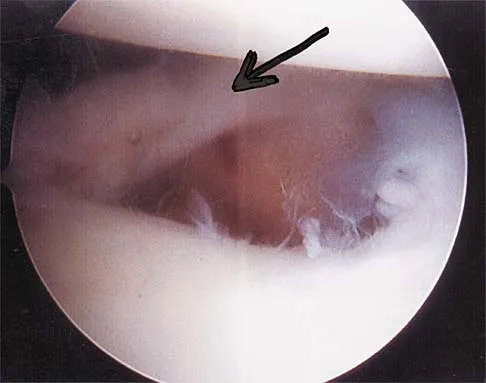

Figure 4a shows the radiograph of a 20-year-old man who has an injury to the right shoulder. Figure 4b shows an arthroscopic view (posterior portal). The arrow points to a

The radiograph shows an anterior dislocation of the shoulder. A frequently encountered sequela of this is a compression fracture of the posterolateral humeral head, commonly referred to as a Hill-Sachs defect. The arthroscopic view of the glenohumeral joint visualizes the posterior aspect of the humeral head. In the image, the area devoid of cartilage to the right is the bare area. The indentation seen to the left is a Hill-Sachs defect. Matsen FA, Thomas SC, Rockwood CA, et al: Glenohumeral instability, in Rockwood CA, Matsen FA (eds): The Shoulder, ed 2. Philadelphia, PA, WB Saunders, 1998, pp 611-754.

- Mazzocca AD, Noerdlinger M, Cole B, et al: Arthroscopy of the shoulder: Indications and general principals of techniques, in McGinty JB (ed): Operative Arthroscopy, ed 3. Philadelphia, PA, Lippincott Williams & Wilkins, 2003, pp 412-427.